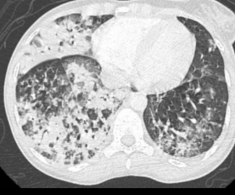

Thorax

- Acute Chest Syndrome: Infarctus pulmonaires (vaso-occlusif, parfois embols graisseux)

- Graves

- Condensations pulmonaires

- Touchant au moins un segment

- Difficile à distinguer d’une infection